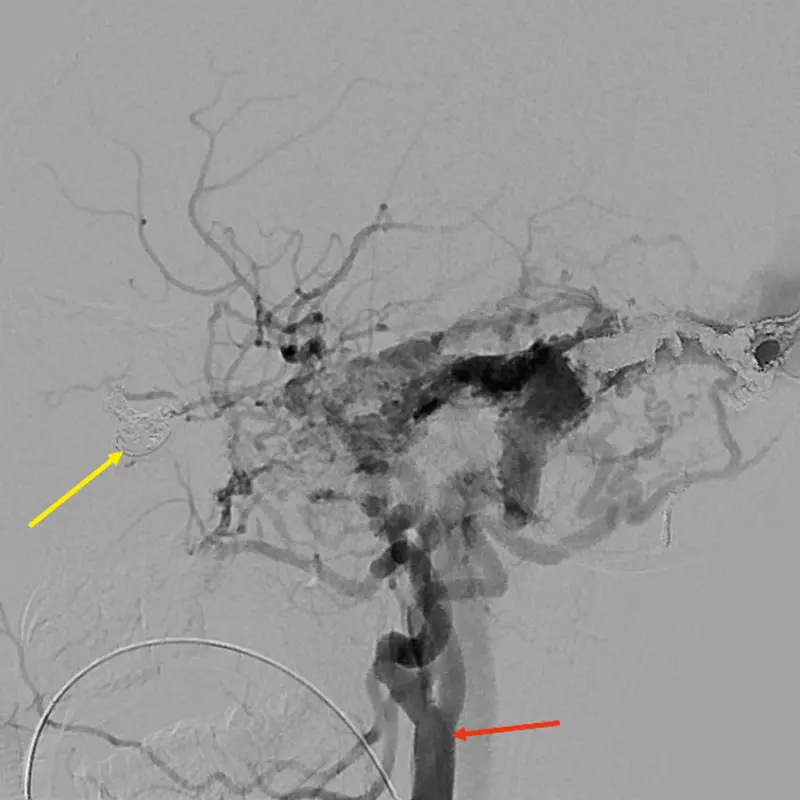

Post-treatment angiogram showing closure of the AV fistula. Yellow arrow: Platinum coil material inside the AV fistula blocking the flow of blood between the artery and vein; red arrow: Right common carotid artery

Dr. Elmalem’s solution was to avoid any incision by gaining access from the face, through one of the dilated vessels that ran medial to the orbit. While the strategy was sound, its execution proved onerous. Every effort to advance a microcatheter through a facial puncture into the vein to allow treatment of the fistula through coil embolization was met with resistance. “We kept trying different areas of the face, and after an hour and a half were finally successful by going through the angular vein that runs between the side of the nose and inner corner of the eyelid,” explains Dr. Elmalem. That cleared the way for Dr. Fifi and her team to close off the faulty connection between vein and artery with a metallic occluding coil.

Integral to the delicate surgery was a sophisticated neuronavigational system at Mount Sinai that NYEE was able to tap into. Specifically, the hospital’s fluoroscopy-guided angiography allowed both teams of surgeons to pinpoint the precise location of the fistula—where the artery connects to the venous pouch—going well beyond just the bony structure normally seen by Dr. Elmalem in her orbital surgery. Throughout the procedure, this technology provided vital 3D guidance to surgeons—including viewing the coils entering the fistula—from their monitors.

Postsurgically, Bryson has continued to make progress. Closing the fistula in the right eye produced a change in his vision from 20/200 to 20/80, with further improvements expected as the left eye is patched for increasingly longer periods to treat his amblyopia.